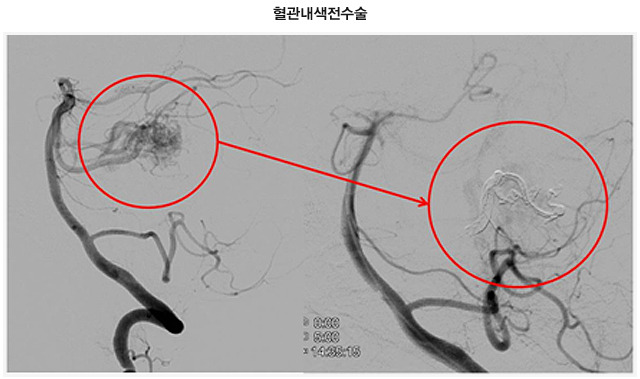

2.2 혈관 내 색전술

카테터를 이용하여 기형 부위에 접착제나 코일을 삽입하여 혈류를 차단하는 방법입니다. 주로 수술 전 출혈 위험을 감소시키기 위해 시행됩니다.